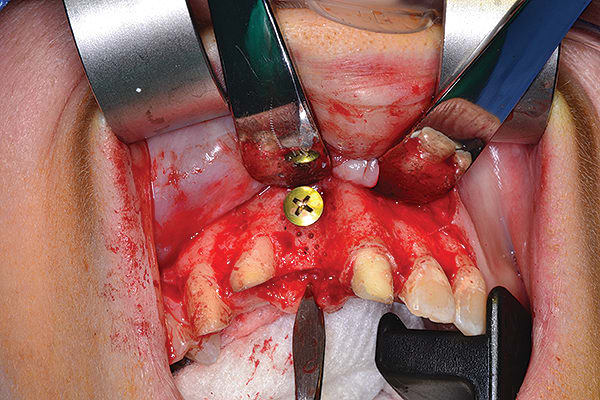

Figure 15

Figure 15 3-mm healing abutment was placed in order to provide a “framework” for epithelization to occur coronally (semi-submerged technique).